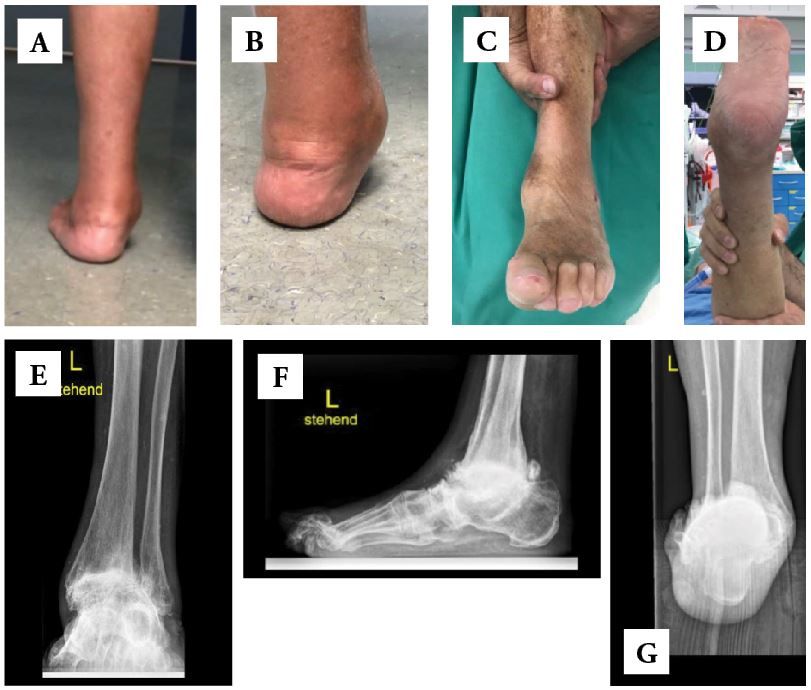

• Severe hindfoot arthritis with significant deformity or instability (Figs. 1-A through 1-G).

• Preoperative radiograph of the ankle (ap and lat view)

• Salzmann view of the ankle to assess the valgus or varus deformity of the heel

• Full leg radiograph (HKA) to determine limb axis

• Radiographs of the fore foot to determine combined foot deformity.